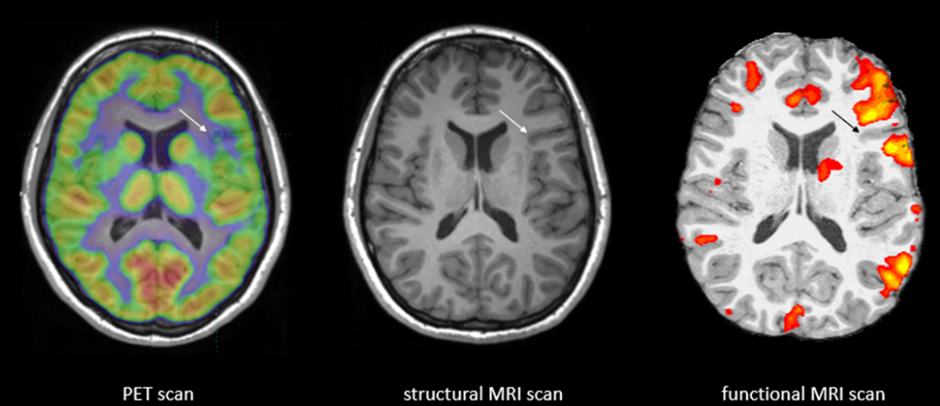

Christian Keysers, director of Groningen’s neuroimaging center, focuses not on psychopathy itself but on the mechanisms of empathy: how observing another’s pain triggers corresponding neural activation in our own brains. He asks whether the same systems that allow us to feel with others are silent in psychopathy.

Using fMRI, researchers observe which brain regions “light up” in response to emotional cues. In typical individuals, witnessing distress activates networks associated with both emotion and motor mimicry. In Patient 13, these signals may be diminished or absent, offering concrete evidence of the neural basis for emotional detachment.